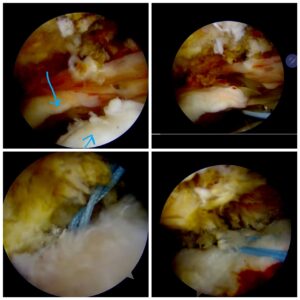

History: A 65 years old man was unable to sleep or put any pressure on his shoulders due to severe shoulder tear.

Case: This man was operated by Dr. Amyn Rajani, Joint Replacement & Arthroscopy Specialist in COVID-19 times. An arthroscopic repair is essential for Supraspinatus tear. Due to having zero strength in Supraspinatis muscle and a full-thickness tear, performing double row repair is much stronger. It will also help the patient in faster recovery as compared to the traditional single-row repair procedure. Physiotherapy can begin after 3 weeks post the surgical procedure to regain complete movement of the shoulder.